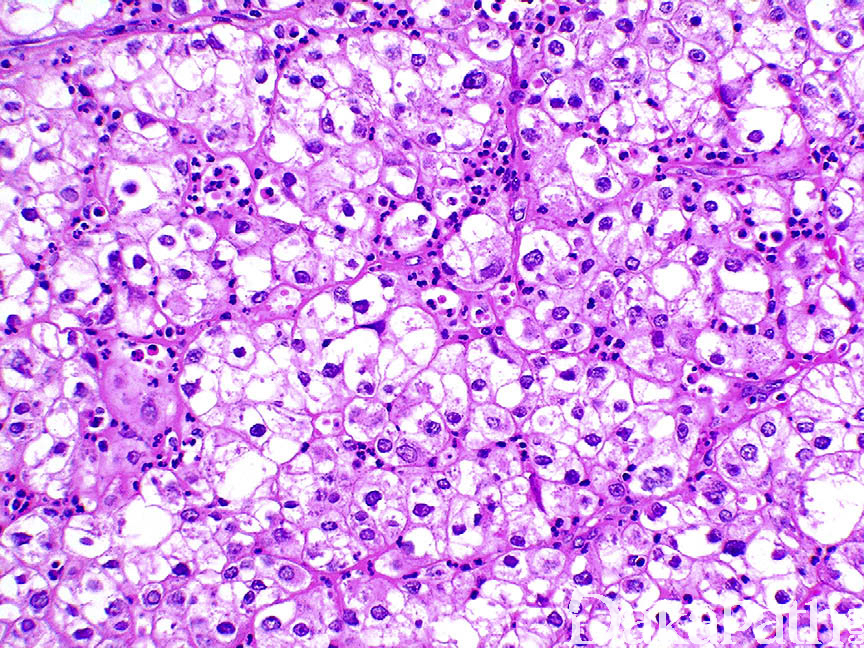

浸润性尿路上皮癌,富脂质

Infiltrating urothelial carcinoma, Lipid-rich

尿路上皮癌瘤细胞胞浆内存在多个空泡挤压核形成类似于脂肪母细胞的瘤细胞

特征性形态学改变是存在大的脂肪母细胞样细胞,具有 1 个或多个胞浆空泡,挤压细胞核;

电子显微镜证实胞浆内存在脂质。